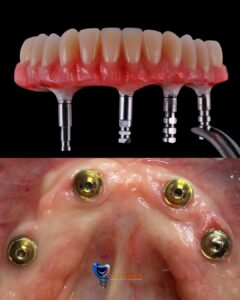

Desde prótesis parciales hasta prótesis completas, tenemos la solución ideal para recuperar tanto la funcionalidad como la estética de tu boca.

Usamos materiales resistentes y estéticos para garantizar que tu prótesis se vea y funcione como dientes naturales.

Ofrecemos prótesis dentales fijas y removibles diseñadas específicamente para ti, asegurando un ajuste perfecto y una sonrisa natural.

Prótesis dentales reemplazan dientes faltantes, pueden ser parciales o completas.

Cuando estés en presencia de ausencias dentarias, y estas pueden ser reemplazadas de distintas maneras entre ellas tenemos el grupo de las fijas y el grupo de las removibles, así como también realizamos prótesis de mayor envergadura como coronas sobre implante y prótesis hibrida.